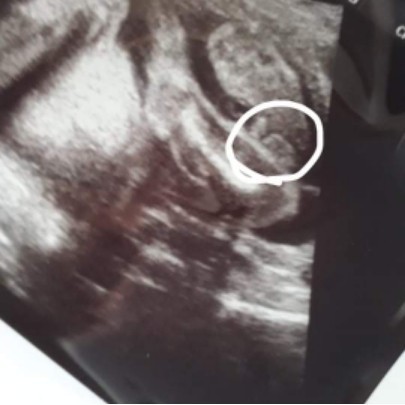

ใช่ผู้ชายไหม

แบบนี้ผู้ชายใช่ไหมคะ

เหมือนนิ้วมือเลยค่ะแม่

น้องไดมอนด์